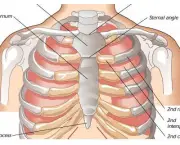

As dores da Costocondrite são causadas por uma inflamação da cartilagem que faz a ligação entre as costelas e osso do peito. Existem níveis dessa doença indo desde leve até uma irritação extremamente dolorosa. As pessoas que sofrem dessa doença chegam a definir a dor como uma sensação de queimadura intensa.

Dentre os principais sintomas dessa doença estão a dor na parede e na caixa torácica. Essa dor costuma piorar com a realização de atividades e exercícios. Uma pessoa que tem Costocondrite pode sentir uma dor muito intensa ao respirar fundo pelo fato que dor se espalha pela cartilagem inflamada. Quando se dá um espirro ou tosse a dor também pode aumentar.

É possível que a dor se espalhe para os ombros e para os braços através dos nervos que se ramificam para longe do peito. Aliás, esse sintoma é que faz com que a Costocondrite se pareça tanto com um problema cardíaco deixando muitas pessoas preocupadas em vão.